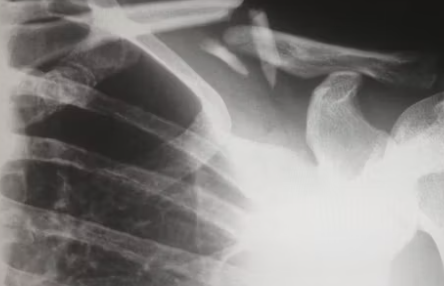

오십견 치료방법을 결정하기 전에 먼저 오십견인지를 진단하는 과정이 필요하겠습니다. 대표적으로 관절 조영술로 검사를 해볼 수 있는데요. 제한된 운동 범위를 확인해 오십견을 진단할 수 있습니다. 오십견 치료방법은 비수술적 치료와 간단한 수술로 분류됩니다.